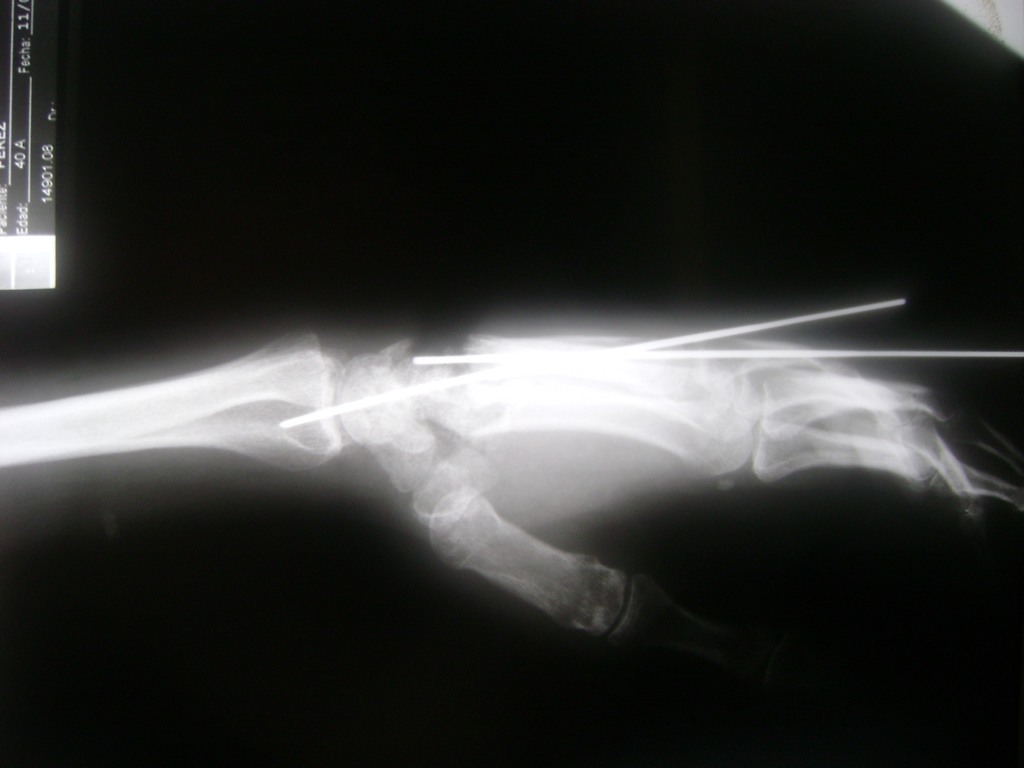

Calcaneo - Cirugías de Muñecas y Manos

Los procedimientos más comunes en cirugía de la mano son aquellos destinados a reparar traumatismos, incluyendo lesiones de tendones, nervios, vasos sanguíneos, y articulaciones; huesos fracturados; y quemaduras, cortes, y otros daños de la piel.